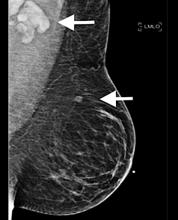

April 9, 2021 — 3-D mammography reduces the number of breast cancer cases diagnosed in the period between routine screenings, when compared with traditional mammography, according to a large study from Lund University in Sweden. The results are published in the journal Radiology.